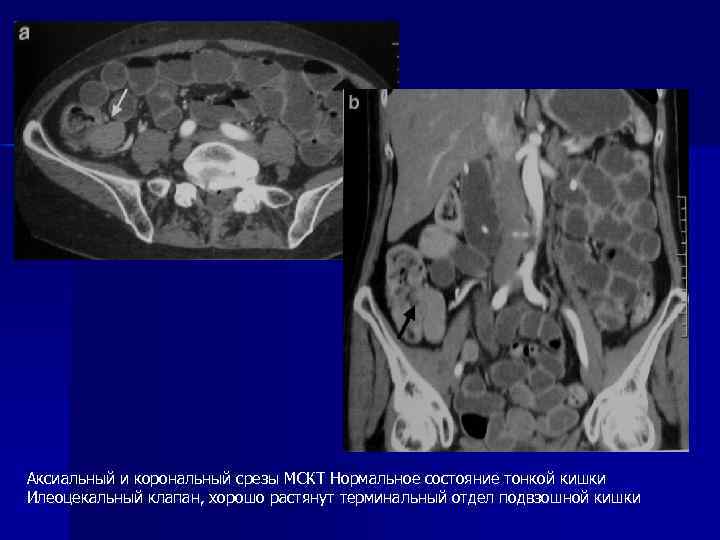

Аксиальный и корональный срезы МСКТ Нормальное состояние тонкой кишки Илеоцекальный клапан, хорошо растянут терминальный отдел подвзошной кишки